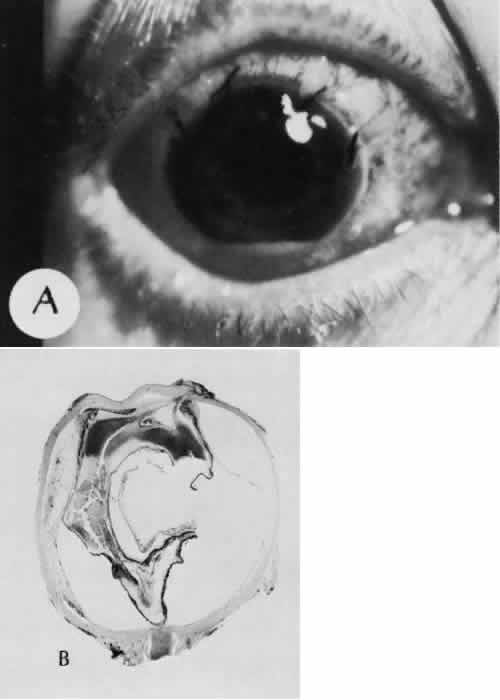

Fig. 24. An unusual complication of cataract surgery. A. An unsuspected uveal mass was noted in the region of the pupil following cataract extraction. The mass was determined to be a metastatic carcinoma. The globe was enucleated. B. In a section of the enucleated globe, extensive tumor (T) can be identified though one hemisphere of the choroid, causing a secondary retinal detachment (RD). The detached retina is herniated through the cataract wound. (Hematoxylin-eosin stain; × 5.)

CATARACT EXTRACTION